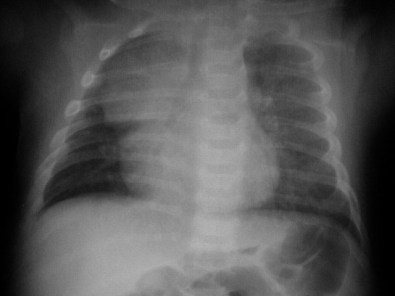

SIGNO DE LA VELA TÍMICA

En la radiografía anteroposterior de los recién nacidos, el timo normal puede verse como una densidad paramediastínica, más frecuente en el lado derecho, con forma triangular o de vela de barco. En la imagen las flechas señalan el timo.

No debe confundirse este signo de la vela tímica con el signo del spinnaker o de las alas de ángel, que se ve en el neumomediastino del neonato y corresponde al timo levantado por el gas mediastínico (Ver Signos de tórax / mediastino).

SIGNO DE LA OLEADA TÍMICA

Las impresiones costales sobre el timo producen un borde ondulado de éste en la radiografía de tórax del recién nacido. Esto permite distinguir el timo normal de los tumores tímicos y otras masas mediastínicas anteriores, que tienen una consistencia dura y no presentan la indentación costal.

SIGNO DE LA ESCOTADURA

En la radiografía del signo de la oleada tímica también puede verse una escotadura o muesca (notch sign) entre el timo normal y la silueta cardiaca. Esta imagen es, pues, un signo de normalidad que nos permite reconocer el timo.